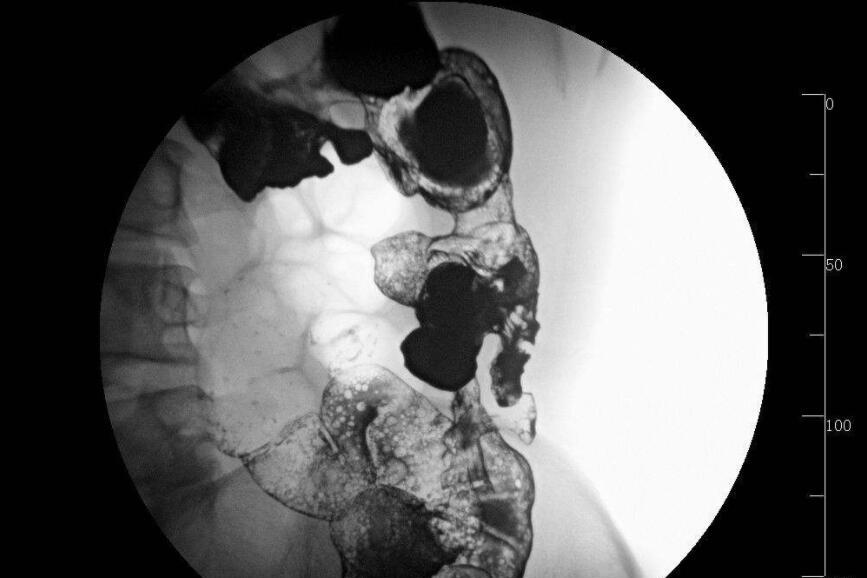

结肠炎是一种炎症性肠病,一般包括溃疡性结肠炎和克隆氏症,下面来详细了解下结肠炎的症状有哪些。

结肠炎的病徵和症状因人而异。由于结肠炎通常会先恶化然后缓解,因此其病徵和症状会随时间改变。

结肠炎的症状包括:

直肠出血

大便时排出黏液

痛楚及不适,包括腹部抽搐

经常感到需要排便

腹泻

疲劳

食慾不振

体重下降

如果发炎加剧并扩散至整条结肠,可能会引起致命的「毒性巨结肠症」併发症。此病症会使结肠快速扩张,并引致严重腹胀、败血病和因肠道穿孔而造成的腹膜炎,并需要立即进行外科手术治疗。